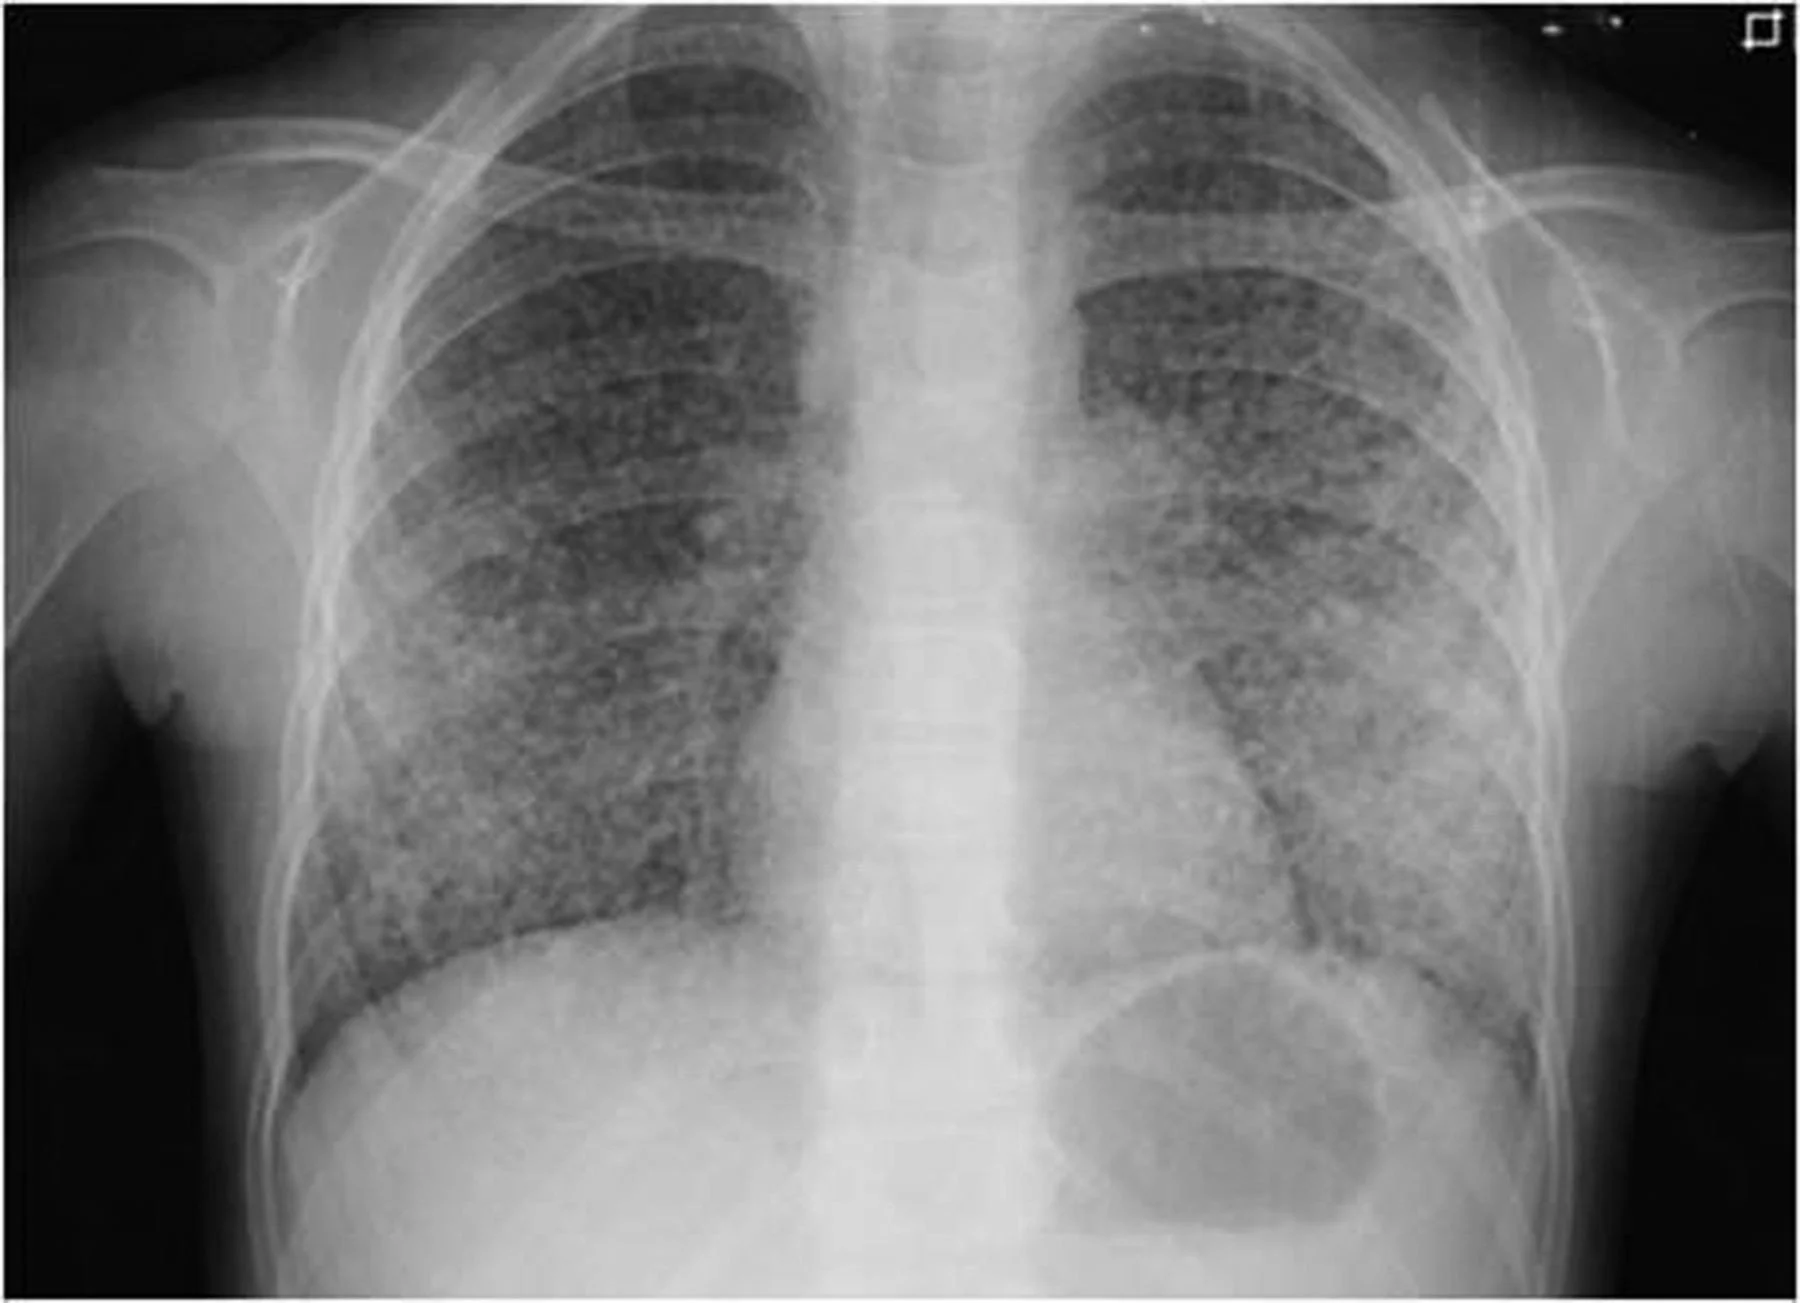

BCG does not prevent primary infection. A child vaccinated with BCG can still be infected if they breathe in the bacteria. However, BCG is highly effective (60–80%) at preventing the hematogenous spread of the bacteria. This means it acts as a "shield" against the most lethal forms of pediatric TB: Miliary Tuberculosis and TB Meningitis [1].

Figure 1. Chest radiograph of a pediatric patient with Miliary Tuberculosis. Note the diffuse, millet-seed-sized nodules throughout both lung fields. This is the specific lethal form of the disease that the BCG vaccine effectively prevents.

(Source: Centers for Disease Control and Prevention (CDC), Public Health Image Library, ID #3428).